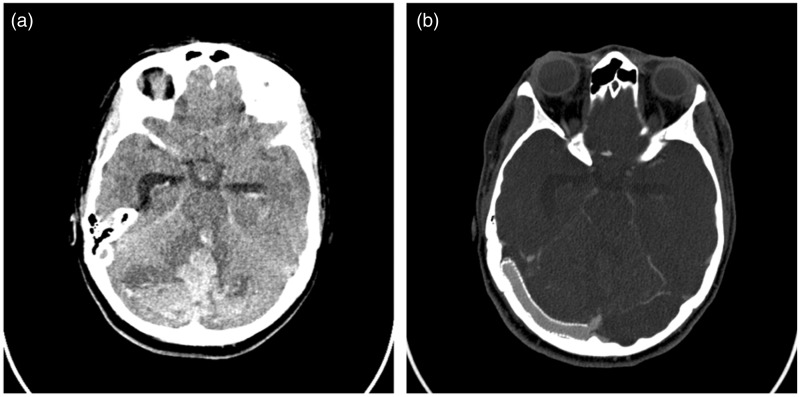

Figure 2.

(a) Unenhanced head computed tomography (CT) showing bilateral cerebellar hemorrhage, intraventricular hemorrhage and acute obstructive hydrocephalus. (b) CT angiography showing right transverse sinus stent patency.